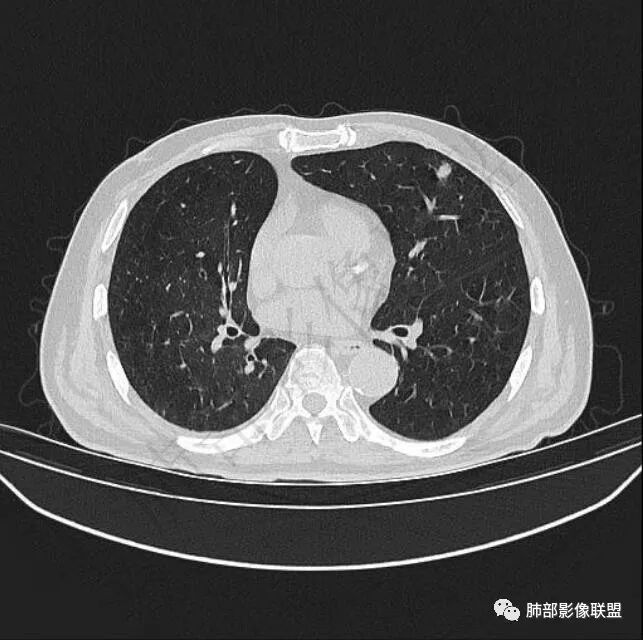

二..发现左肺上叶舌段实性密度小结节影,不规则略呈半环形,边界清楚,未见分叶、毛刺及磨玻璃晕。未见卫星病灶。